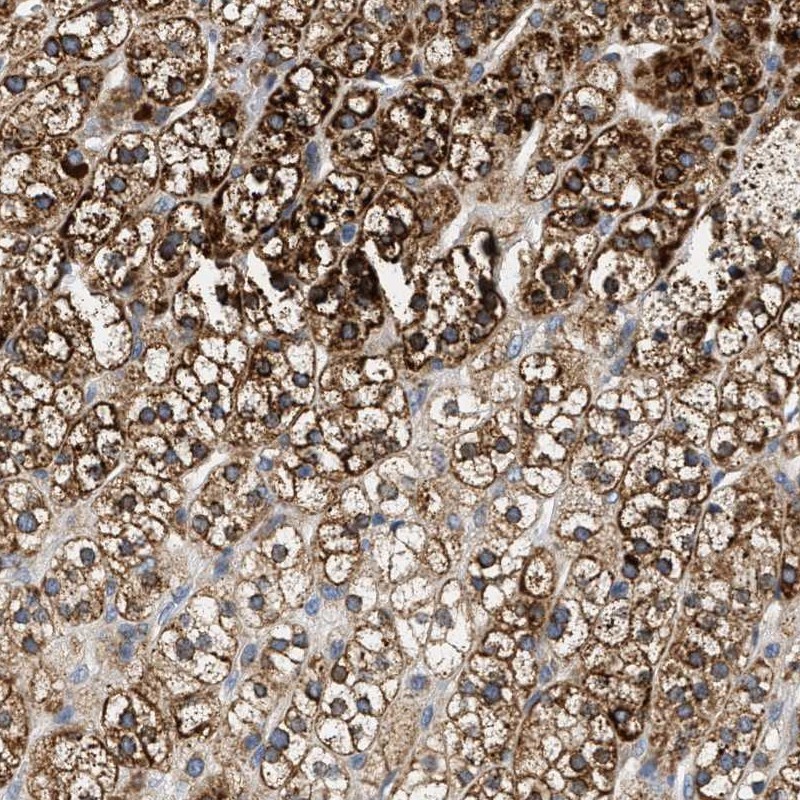

Immunohistochemical staining of human adrenal gland shows strong cytoplasmic positivity in glandular cells.